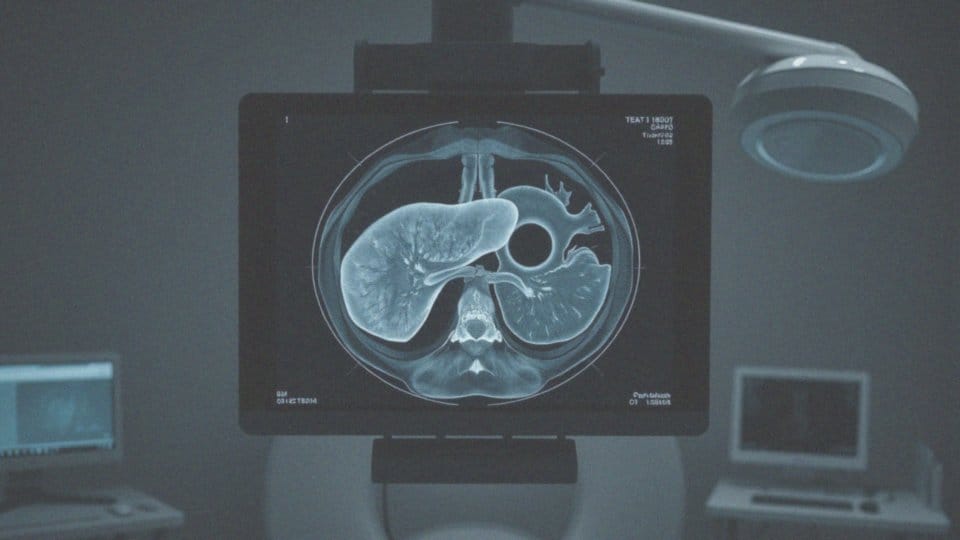

Zmiana hipodensyjna w wątrobie to obszar, który na obrazach z tomografii komputerowej (TK) pochłania mniej promieniowania rentgenowskiego niż okoliczna tkanka. Tego typu zmiany mogą wskazywać na różne schorzenia, w tym nowotwory, co sprawia, że ich analiza jest istotnym elementem diagnostyki obrazowej.

Diagnostyka hipodensyjnych zmian w wątrobie opiera się na wykorzystaniu różnych technik obrazowych, które pozwalają lepiej zrozumieć charakterystykę tych zmian oraz związane z nimi ryzyko. Pierwszym krokiem zwykle jest ultrasonografia (USG), która umożliwia wstępną ocenę, ustalenie lokalizacji i określenie ogólnych cech zmian. Jeśli wyniki USG są niewystarczające, lekarze mogą zlecić tomografię komputerową (TK) z kontrastem, co umożliwia dokładniejszą analizę unaczynienia oraz rozmiarów zmian. Ta informacja jest szczególnie istotna w kontekście diagnostyki nowotworów i innych patologii.